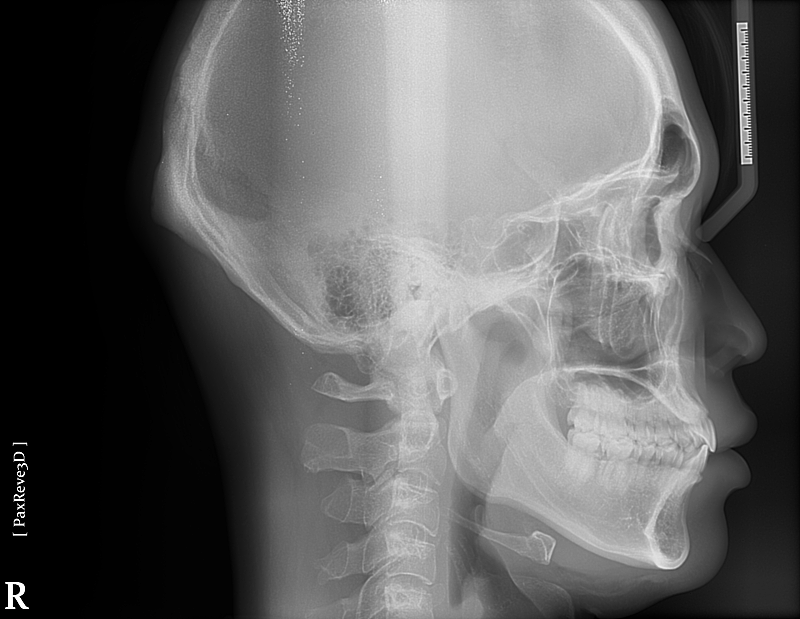

턱이 비율상 대각으로 긴가요?

사진찍으면 턱이 대각으로 긴 느낌과 돌출입 느낌이 있어서 대략적인 판단부탁드립니다

• 3번 째 사진

해당 골격 정도로는 비대칭이라고 보지 않습니다. 너무 예민하게 반응하시는 것으로 보이며 이정도는 정상 범주입니다. 연조직을 보지 않더라도 심미적으로 크게 문제가 되지 않을 것으로 보이며 미세 조정을 원한다면 담당 교정과 선생님과 상담을 해보시길 바랍니다.

사진상으로는 크게 문제는 없어 보입니다. 정확한 판단을 위해서는 교정진단을 통해서 정상 범주와 비교를 해보는게 좋습니다.